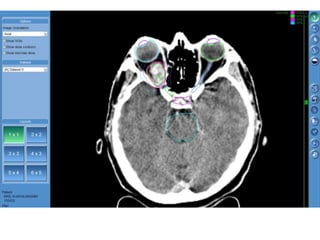

RT planning: meningioma

GTV/CTV = residual tumour / tumour bed for gr II / gr III

CTV = 5 mm for benign meningiomas

2 - 3 cms for high grade meningiomas / HPC

PTV = 2mm for SRT

5mm for 3DCRT

All normal structures contoured

Dosage:

Gr-I:

54Gy/30# conformal RT

25Gy/5# / 13Gy/1#

Gr II & III meningioma:

60Gy/30#/6wks

Conformal RT

Grade I Grade II/III

Tharmoplastic mask

CT scan with contrast- 3 mm slice

MRI scan with T1 contrast & T2 flair is a must

RT planning: meningioma GTV/CTV= residual tumour / tumour bed for gr II / gr III CTV = 5 mm for benign meningiomas 2 - 3 cms for high grade meningiomas / HPC PTV = 2mm for SRT 5mm for 3DCRT All normal structures contoured Dosage: Gr-I: 54Gy/30# conformal RT 25Gy/5# / 13Gy/1# Gr II & III meningioma: 60Gy/30#/6wks Conformal RT Grade I Grade II/III Tharmoplastic mask CT scan with contrast- 3 mm slice MRI scan with T1 contrast & T2 flair is a must